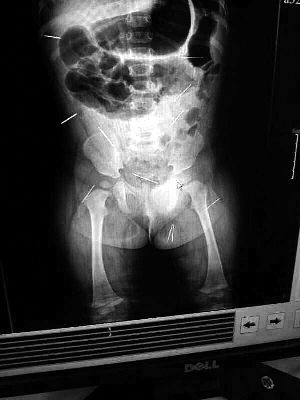

山東聊城11個(gè)月女嬰萱萱(化名)疑似被人以12根鋼針插滿臀部、腹腔等部位,昨天在兒童醫(yī)院會(huì)診后,醫(yī)生稱3根針靠近胸腔最危險(xiǎn),首批先行取出,預(yù)計(jì)將在下周二手術(shù)。孩子父母稱孩子一直由家人照顧,自家與他人并無冤怨。山東警方表示正在偵破中,不便透露案情。

“要不是當(dāng)初那幾個(gè)紅點(diǎn),可能到現(xiàn)在我們還不知道孩子身體里有鋼針!”昨天,在兒童醫(yī)院住院處,萱萱爸爸范先生稱,日前原本很愛笑的萱萱突然變得有些焦躁,一抱起來就哭,孩子母親偶然間在萱萱屁股上發(fā)現(xiàn)了幾個(gè)小紅點(diǎn)兒,原以為是蚊蟲叮咬,就醫(yī)結(jié)果卻讓人不寒而栗?!搬t(yī)院拍出的片子上,萱萱的體內(nèi)有12根鋼針,插滿臀部、腹腔、骨盆等各個(gè)部位?!狈断壬榻B,因?yàn)殇撫樢焉钊塍w內(nèi),要是孩子不哭鬧,他們很難發(fā)現(xiàn)。

北京晨報(bào)記者了解到,目前體內(nèi)的12根鋼針多分布在孩子的臀部,一根在腹部,其余3根在胸腔附近,其中一根很接近心臟?!耙?yàn)楹⒆犹?,醫(yī)生們害怕取針的時(shí)候?qū)λ斐蓚?,在胸腔附近?針可能會(huì)威脅她的生命”。